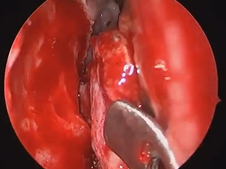

Microdirect Laryngoscopy and CO2 Laser Total Vestibulectomy for Pyolaryngocele

- Date : 01/01/2020